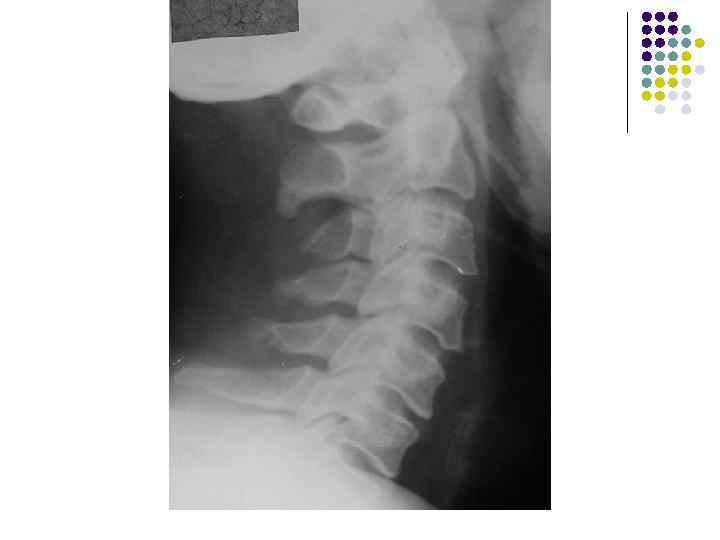

l На рентгенограмме шейного отдела позвоночного столба в боковой проекции определяется: выраженные дистрофические изменения за счет остеохондроза с преимущественными проявлениями в сегменте С 5 -6 – сужение и деформация межпозвонковых пространств, выраженный субхондральный остеосклероз, значительные костные разрастания по краям тел позвонков. Выпрямление физиологического лордоза. Признаки нарушения положения тела С 4 (симптом «распорки» )

l На рентгенограммах шейного отдела позвоночного столба в двух проекциях определяется комплекс выраженных дистрофических изменений с преимущественными проявлениями в сегментах С 5 -6 -7 в виде остеохондроза и выраженного спондилоза за счет неравномерного сужения межпозвонковых пространств, субхондрального отсеосклероза и костных разрастаний как по краям тел позвонков с продолжением плоскости замыкательной площадки, так и под передней продольной связкой с образованием мощного костного соединения. Положение тел позвонков правильное, деструктивных изменений нет.